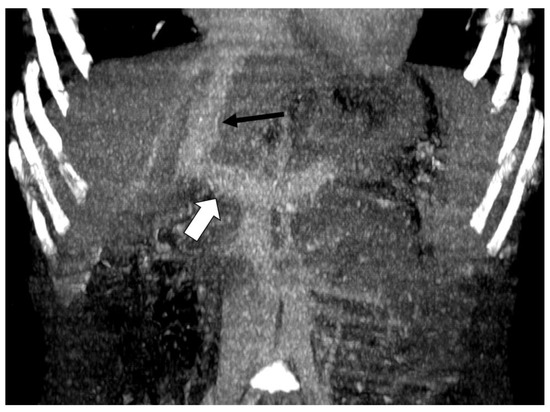

2.3. Case C (Dog)

2.4. Case D (Dog)